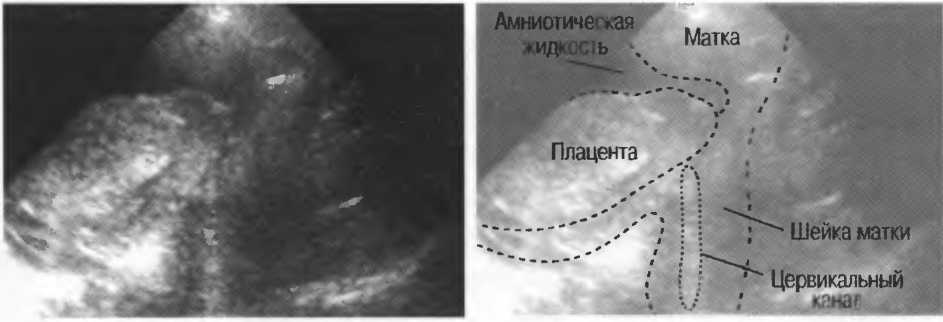

Реверберации могут полностью менять изображение, создавая линейные структуры или зеркальное отображение. Например, реверберации между параллельными слоями подкожных тканей создают параллельные линейные структуры в мочевом пузыре (рис. 20в).

Рис.20в. При сканировании матки через наполненный мочевой пузырь параллельные датчику слои тканей передней брюшной стенки могут вызывать появление ревербераций, которые определяются как зхоструктуры в передних отделах мочевого пузыря на фоне анэхогенной полости. Поперечный срез (слева) отличается от продольного среза (справа) при изменении положения датчика.